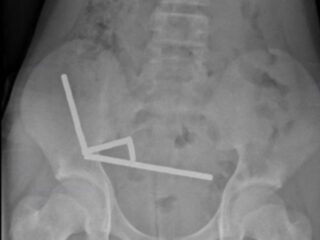

ニュージーランドの病院に、激しい腹痛を訴える13歳の少年が運び込まれた。問...